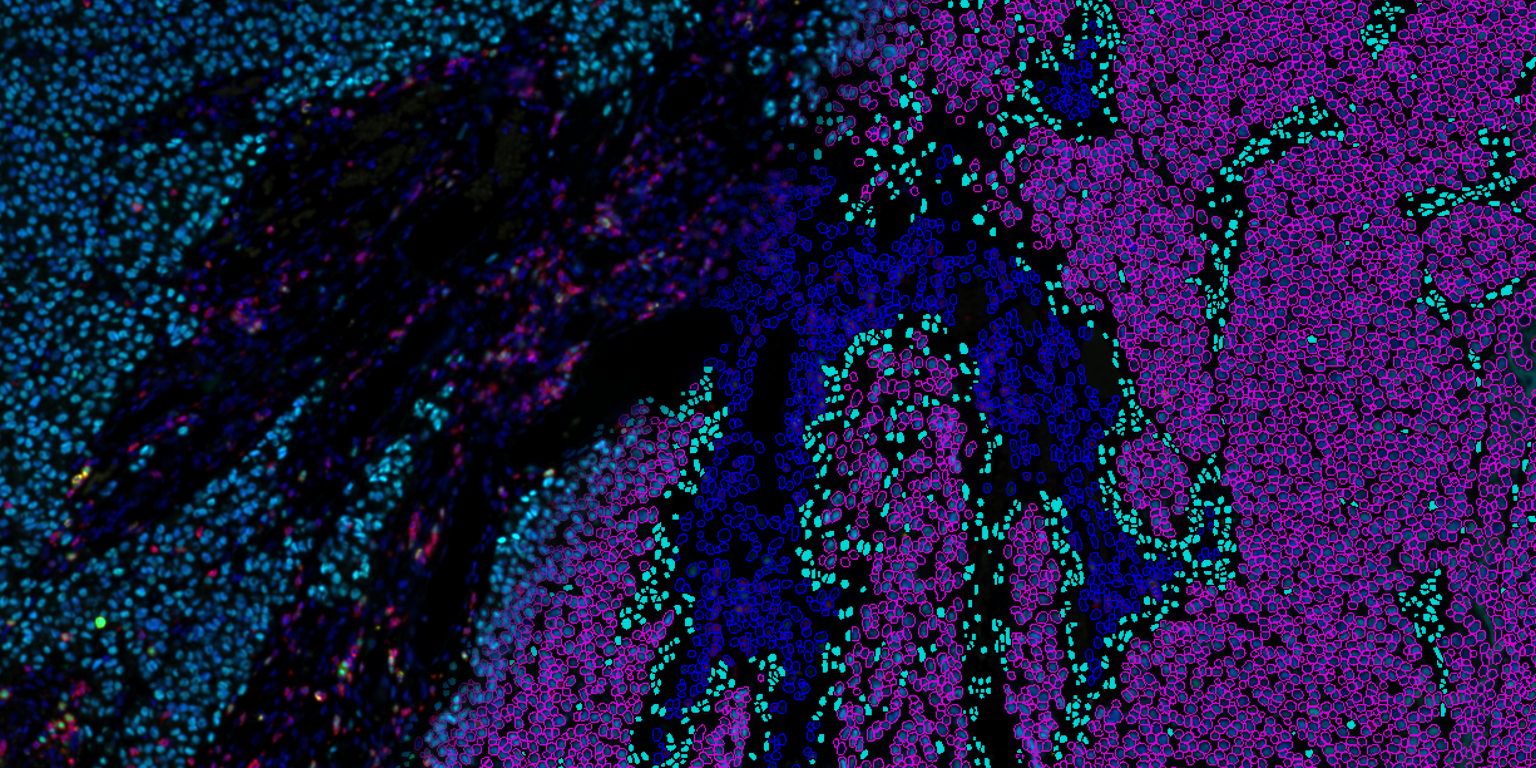

Visiopharm’s pioneering image analysis tools support thousands of scientists, pathologists, and image analysis experts in academic institutions, biopharmaceutical industry, and diagnostic centers. AI-based image analysis and tissue mining tools support research and drug development research worldwide, while CE-IVD APPs support primary diagnostics. With the most advanced and sophisticated artificial intelligence and deep learning, Visiopharm delivers tissue data mining tools, precision results, and workflows.